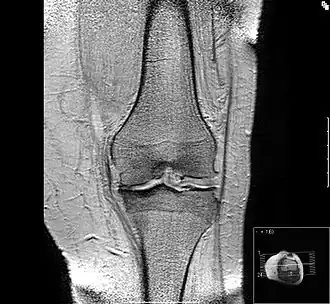

Вторая стадия неизбежно переходит в третью — стадия тяжёлого артроза. Её признаки — выраженная костная деформация опорной площадки сустава, которая изменяет ось конечности. Несостоятельность, укорочение связок сустава приводит к патологической подвижности сустава или в сочетании с жёсткостью суставной сумки — к резкому ограничению естественных движений — контрактур. Хроническое воспаление и хронический болевой синдром обычно сопровождают 2 и 3 стадию.

Исход артроза — полное разрушение сустава с формированием анкилоза — полной неподвижности сустава или неоартроза с неестественной подвижностью. Это сопровождается тяжёлым нарушением функции конечности. В последнее время, не дожидаясь исхода заболевания, всё чаще применяют специальные операции по замене сустава протезом — эндопротезирование сустава. На рисунке изображена типичная для терминальной стадии артроза коленного сустава варусная деформация колена в сочетании с боковой патологической нестабильностью коленного сустава. Артроз блоковидного или шаровидного сустава, такого как тазобедренный, завершается анкилозированием. При этом замыкание сустава обычно происходит в нефизиологическом (порочном) положении конечности. В данном случае мы видим бедро в положении сгибания и приведения, при котором нога укорачивается, а ось конечности и биомеханика опорно-двигательной системы существенно нарушается.

Рентгенологическая семиотика остеоартроза складывается из признаков, отражающих дистрофические изменения в суставных хрящах (сужение суставной щели) и в костной ткани (уплощение и деформация суставных поверхностей, кистовидные образования), нестабильность суставов (подвывихи, искривления оси конечностей), реактивные компенсаторно-приспособительные процессы (краевые костные разрастания, субхондральный остеосклероз).

Сужение суставной щели свидетельствует о значительных изменениях суставных хрящей. Суставная щель может стать клиновидной, суживаясь с одной стороны и нередко расширяясь при этом с противоположной, что указывает на недостаточность связочного аппарата и нестабильность сустава.